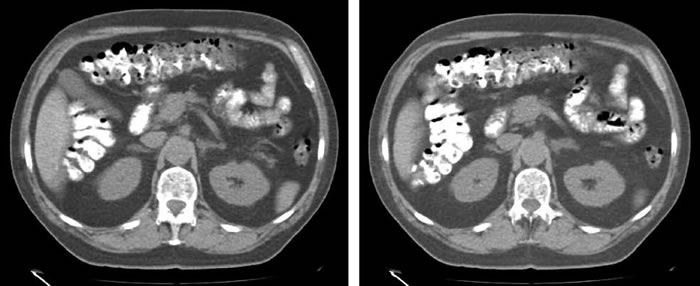

Paciente con antecedente de hipertensión arterial grave que, en un estudio realizado 4 años antes, demostró tener hiperaldosteronismo primario, certificado por elevación de aldosterona plasmática (25,6 ng/dL), supresión concomitante de ARP (<0.2 ng/mL/h) y elevación de la relación AP/ARP (85,3). Además, presentaba hipokalemia (2,7 mEq/L), natremia (140 mEq/L) y funcion renal normal (creatinina 0.87 mg/dL). El estudio con TAC de abdomen mostro engrosamiento nodular de ambas glandulas suprarrenales, siendo este mas notorio a izquierda (Figura 1). Quedo en tratamiento con Espironolactona 50 mg/d, Enalapril 10 mg/d y Amlodipino 10 mg/d. Evoluciono con ginecomastia bilateral progresiva, sintomatica, por lo que fue derivado a Endocrinologia para reevaluacion del hiperaldosteronismo. Suspendida la Espironolactona, se solicitaron nuevos examenes: Aldosterona 40,2 ng/dL, ARP 0,6 ng/mL/h, AP/ARP: 67, sodio 140 mEq/L, potasio 4.5 mEq/L. Dada la gravedad de su hipertension no se efectuo una prueba confirmatoria con fludrocortisona o infusion salina. La RM de abdomen mostro ambas glandulas suprarrenales hiperplasicas de tipo multinodular, con predominio a izquierda y con un nodulo de 19 mm de diametro. Para completar el estudio se realizo un CVS con infusion de ACTH (50μg/h), que fue satisfactorio y concluyo hipersecrecion de aldosterona de la glandula derecha, sin supresion de la glandula izquierda (Tabla 1a), concluyendose que se trataba de una hiperplasia suprarrenal bilateral. Se inicio tratamiento con Epleronona.

Figura 1. RM de abdomen que muestra (indicado con flechas) crecimiento multinodular de ambas glándulas suprarrenales, con predominio a izquierda; nódulo mayor 19 mm de diámetro.

Los dos casos clínicos presentados ilustran la importancia del CVS para aclarar el diagnóstico etiológico del HAP. En el primer caso, las imágenes de la TAC mostraban compromiso bilateral pero con un nódulo predominante en el lado izquierdo, que no se correspondía funcionalmente con lo obtenido en el cateterismo venoso que demostraba lateralización a derecha. En el segundo caso, el paciente tenía un nódulo suprarrenal derecho de 11 mm, con correspondencia funcional, ya que lateralizaba al mismo lado en el CVS, permitiendo efectuar una suprarrenalectomía derecha exitosa.

Estos resultados son concordantes con casuísticas que demuestran que la TAC sólo tiene, en el mejor de los casos, una sensibilidad de 78% y una especificidad de 75% para determinar lateralización7,9. Las limitaciones de la TAC son más notorias en pacientes mayores de 40 años, por la mayor frecuencia de incidentalomas suprarrenales en ese grupo etario con respecto a individuos más jóvenes. También el examen está limitado cuando se sospecha bilateralidad, como ocurrió en uno de nuestros pacientes (Caso 1).